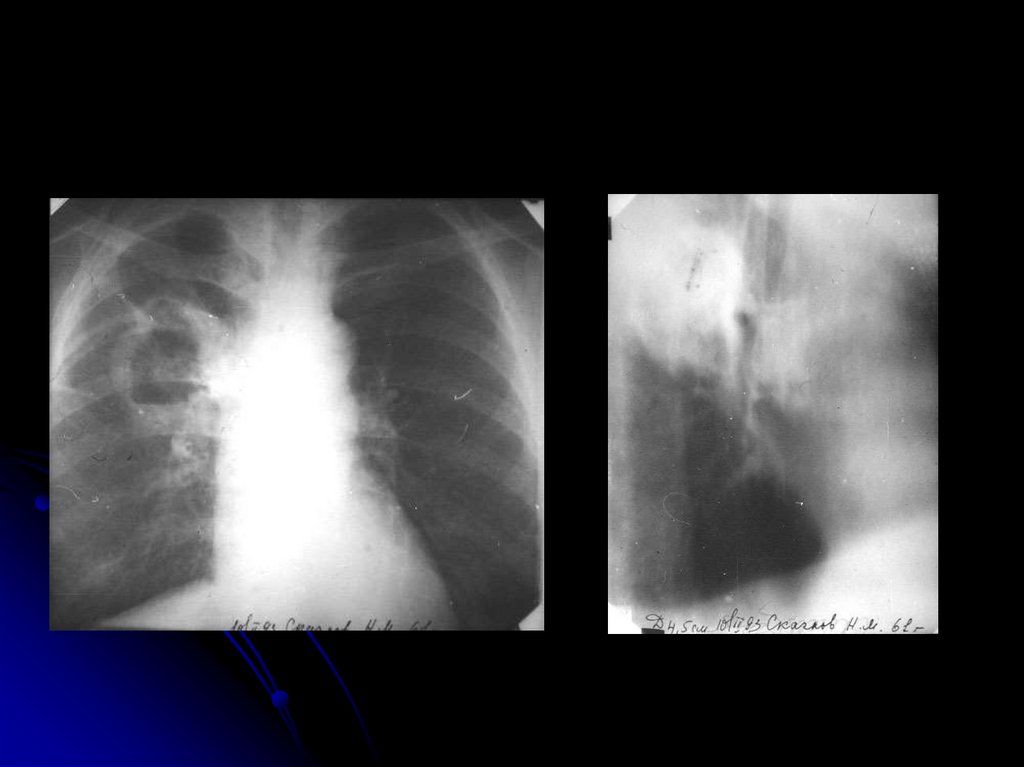

После прорыва

8. После прорыва

Блокированные абсцессы

9. Блокированные абсцессы